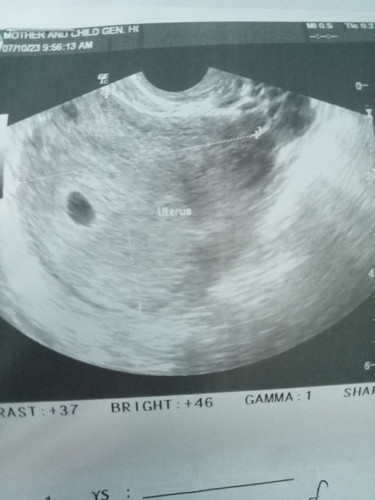

Hello, ultrasounds have interpretations attached to them and those are what doctors read so they can explain whatever findings they have on you.